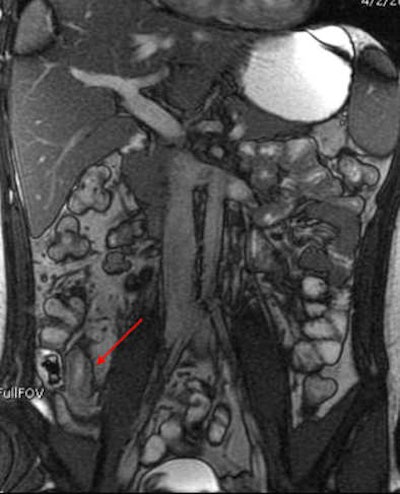

MRI results were then compared to colonoscopy and pathology reports to determine the presence or absence of disease in evaluable bowel segments. Individual imaging parameters (including wall thickening, enhancement, T2 signal, mesenteric vascular prominence, and adenopathy) were also separately analyzed to determine their independent predictive value, the authors wrote.

The study team acquired steady-state free-precession (SSFP) images of the abdomen and pelvis (TR= 4 ms, TE = 2 ms, slice thickness 8 mm for coronal images and 8-mm for axial images). Axial and coronal fat-suppressed half-fourier single-shot fast-spin echo (SSFSE) and axial spoiled-gradient images were also obtained through the abdomen, followed by T1-weighted fat-suppressed spoiled-gradient echo (LAVA/VIBE) images, before the injection of 1 mmol/kg of gadopentate dimeglumine contrast (Bayer Healthcare) followed by a saline flush and postcontrast imaging.

Mild pathologic changes are more difficult to detect with MRE or any other imaging test compared to severe changes, the authors wrote. Thus, the sensitivity of MRE for detection of pathologically mild disease was 68% in the terminal ileum and 27% in the colon, versus 87% in the ileum and 88% in the colon for severe disease. The negative predictive value of MRE was 89% for distal ileal disease and 96% for colonic disease, "indicating that MRE may successfully exclude active Crohn's disease," Grand and colleagues stated.

Interestingly, the results were in line with smaller studies that used antiperistaltic agents, they wrote. As in those studies, MRE showed its real strength in a couple of features of active Crohn's disease. "Analysis of individual MR parameters demonstrates that wall thickening and abnormal enhancement are the most sensitive indicators of Crohn's disease on MRE while abnormal T2 signal, mesenteric vascular engorgement, and adenopathy were insensitive but specific," he wrote.